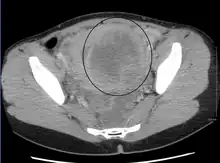

![]() | |

| A very large (9 cm) fibroid of the uterus which is causing pelvic congestion syndrome as seen on X-ray computed tomography | |